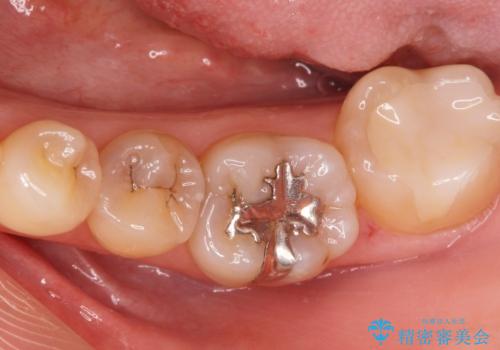

- 前歯の見た目が気になるとの事で来院。

根の治療のやりかえは希望されなかったので土台だけやりかえを行い、ジルコニアクラウンで治療を行いました。